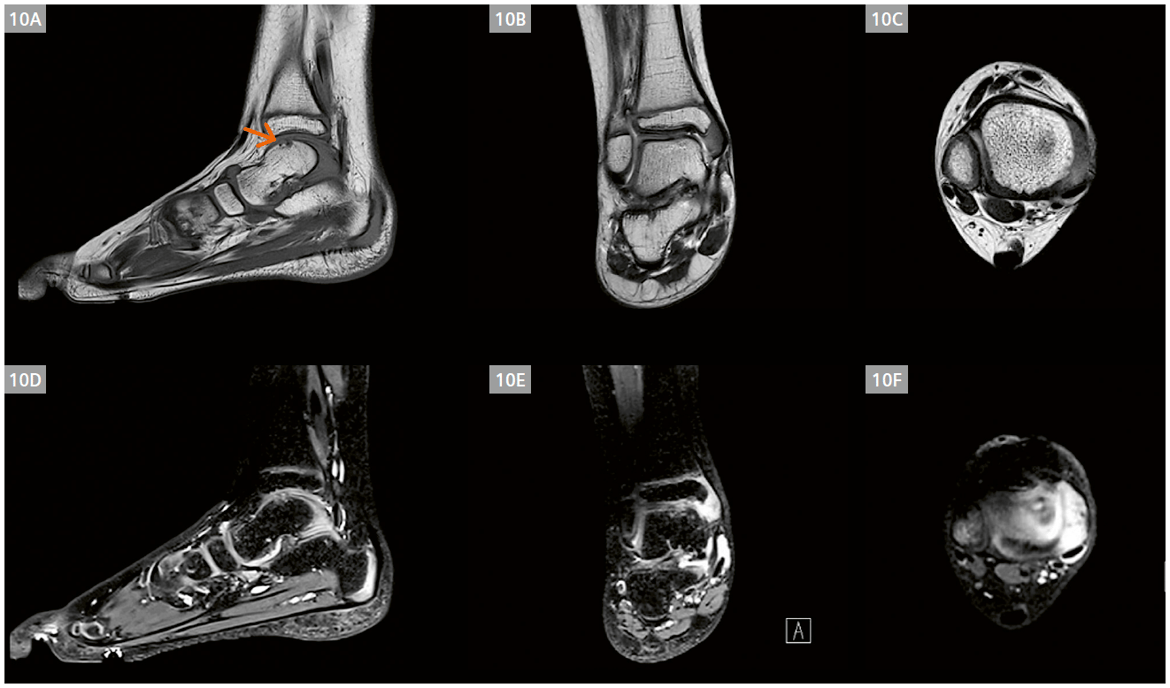

A 6-year-old girl with known polyarticular juvenile idiopathic arthritis in the right ankle. Her first MRI ankle exam was performed without sedation on our 3T MAGNETOM Skyra when she was 5 years old. She had an initial evaluation and treatment for the right ankle (Fig. 10) and is returning for re-evaluation of the same ankle. Additionally, there is a request to assess the left ankle during this visit. With the latest techniques provided by our 3T MAGNETOM Vida Fit, we were able to examine both ankles with a gadolinium injection. The right ankle shows synovitis at the first metatarsophalangeal (MTP) joint, and osteochondral lesion at the talus (Fig. 11). Imaging of the left ankle indicates synovitis of the talonavicular joint (Fig. 12).

(10A–10F) First examination (right ankle) with conventional imaging acquired on a 3T MAGNETOM Skyra.

- (10A) T1w TSE sag, 0.2 × 0.2 × 3.0 mm3 (interpolated), TA 2:22 min.

- (10B) T2w TSE cor, 0.2 × 0.2 × 3.0 mm3 (interpolated), TA 4:05 min. (10C) T2w TSE tra, 0.2 × 0.2 × 3.0 mm3 (interpolated), TA 2:18 min.

- (10D) PDw 3D SPACE sag, 0.6 × 0.6 × 0.6 mm3, TA 5:00 min.

- (10E) PDw 3D SPACE multiplanar reconstruction (MPR) cor.

- (10F) PDw 3D SPACE MPR tra.